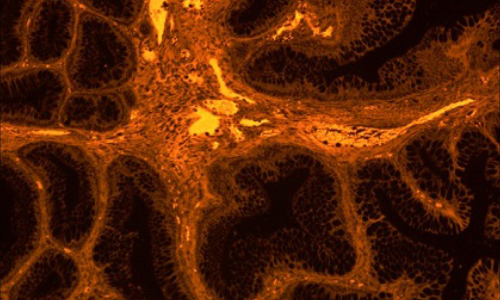

Dhyana 400DC(簡稱:400DC)是一款前照式彩色sCMOS 相機。它兼具科研級靈敏度和真實色彩還原能力,具有寬闊的視野和卓越的動態范圍,即使在弱光下也能拍攝高質量彩色圖像。

采用高靈敏彩色sCMOS圖像芯片,兼具科研級的靈敏度和真實色彩還原能力,無論明場還是暗場拍攝,都能清晰拍攝細節豐富的彩色圖像。